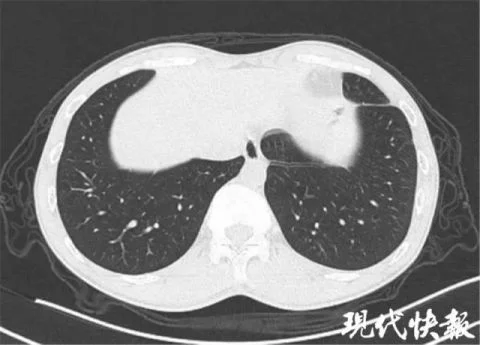

△肺吸虫患者典型的"隧道征"

现代快报记者了解到,肺吸虫病的致病作用主要是由童虫、成虫在组织器官中移行、窜行、定居及分泌物、代谢产物所引起,可累及肝脏、肺、胸、腔、眼、脑、皮下组织等多个组织、器官。换句话说,这些小虫一旦进入人体后,就会在组织器官中到处乱钻,并产生分泌物、代谢产物,时间长了以后,甚至能在肺部钻出一个个"隧道",形成肺纤维化。再加上这种疾病的临床表现复杂多样,缺乏特异性,极易造成误诊,更是增加了诊断的难度。